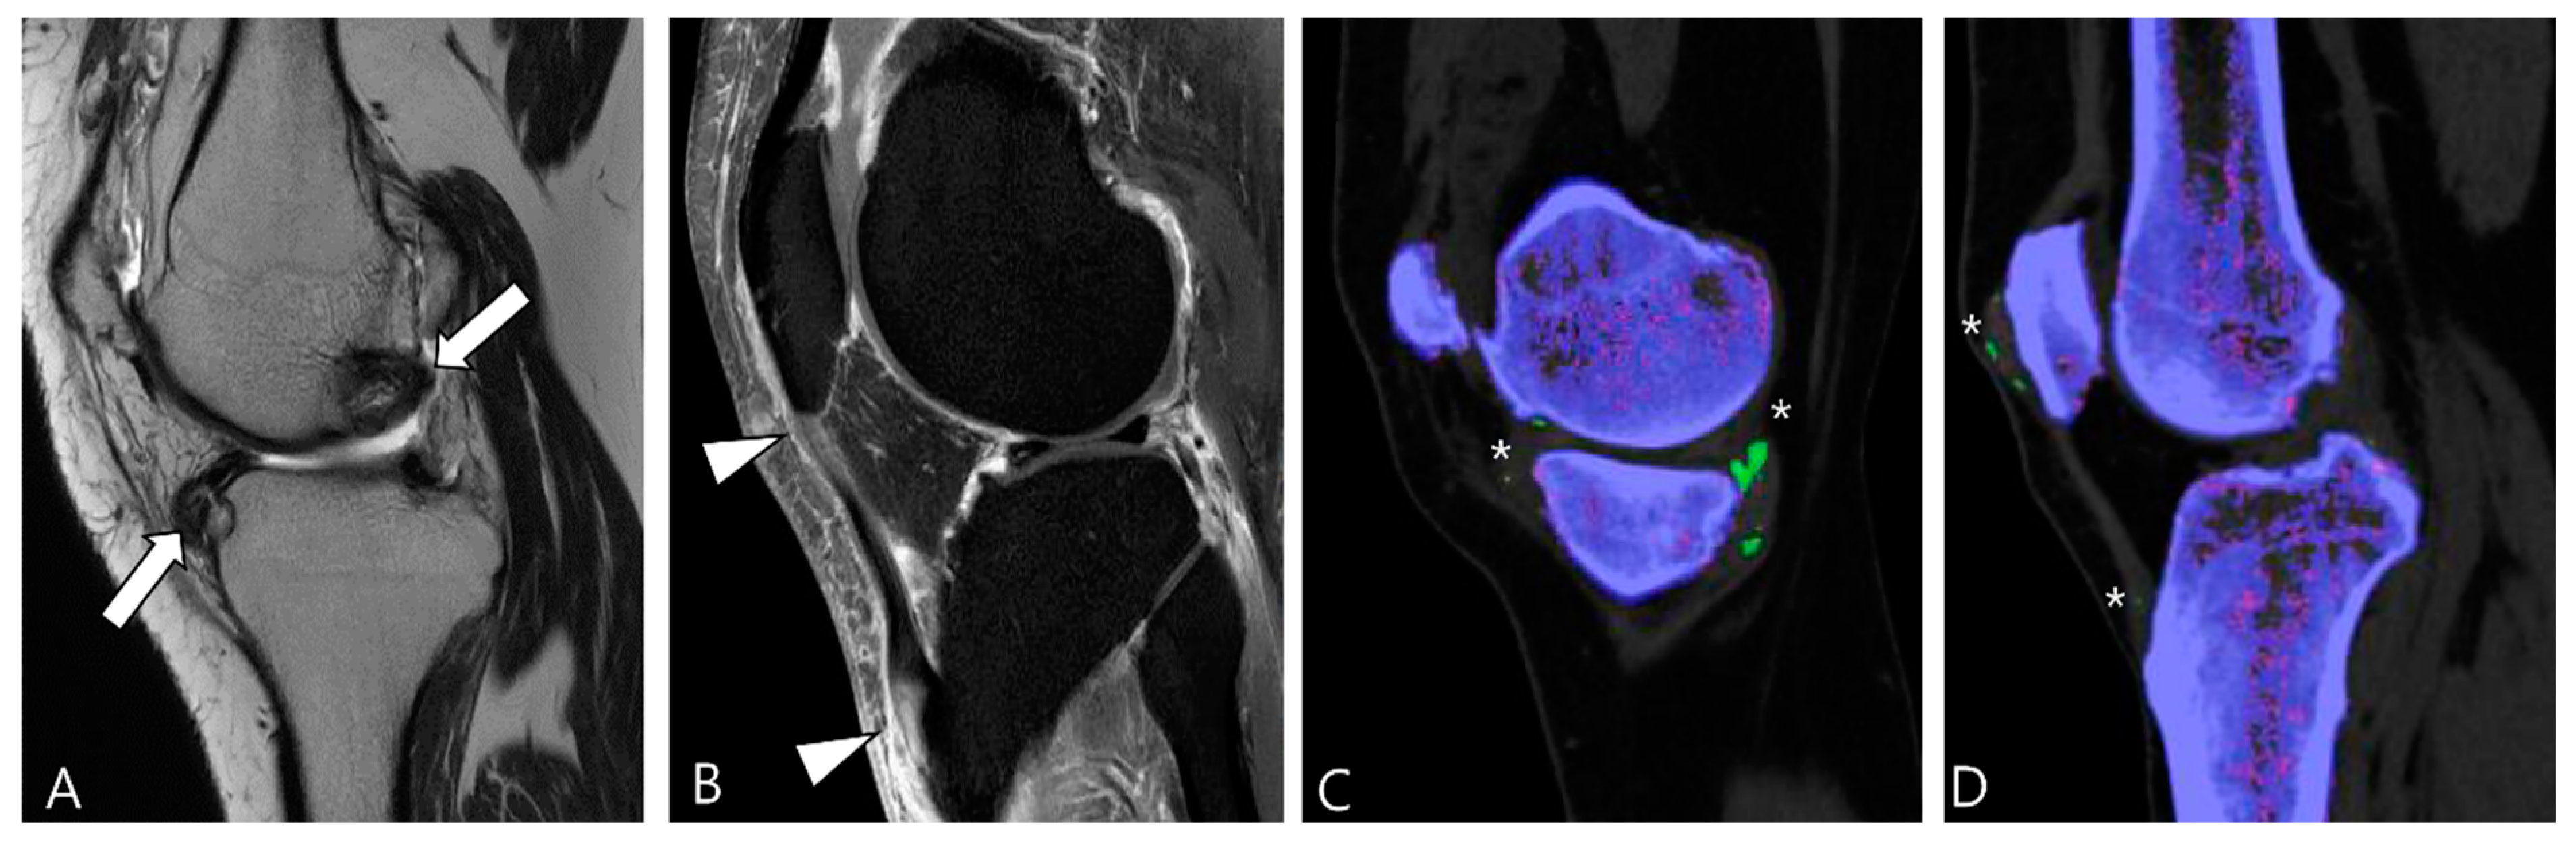

Gout, an inflammatory response triggered by the deposition of monosodium urate (MSU) crystals as a result of hyperuricemia, evolves into its chronic phase known as tophaceous gout, characterized by asymmetric polyarthritic distribution [48]. While tophi are commonly periarticular, they can also involve the articular or bursal synovium [49]. In MRI, intra-articular tophi typically exhibit heterogeneously low SI on both T2WI and T1WI, a feature that may resemble intra-articular D-TSGCT [57]. The degree of enhancement varies due to hypervascular granulation tissue surrounding the tophus or inflammatory tissue within the tophi [54]. Distinguishing gout from D-TSGCT can be aided by typical locations such as the quadriceps, patellar tendon, and Achilles tendon (Figure 14) [49]. Although tophi may show mineralization, calcification is not usually apparent in radiographs [48]. Recently, dual-energy CT has emerged as an alternative noninvasive diagnostic tool for identifying and quantifying MSU crystals (Figure 14) [58,59].

Figure 14.

A 39-year-old male with tophaceous gout of the knee. (A) Sagittal T2WI shows heterogeneously low SI masses along the synovial lining of the knee joint (arrows). (B) Sagittal contrast-enhanced fat-suppressed T1WI shows the abnormal enhancement with nodular thickening of patellar tendon (arrowheads). (C,D) Dual-energy CT reveals MSU crystal deposition (asterisks) with green color coding along the synovial linings and quadriceps-patellar aponeurosis. Trabecular or cancellous bone is displayed in purple.